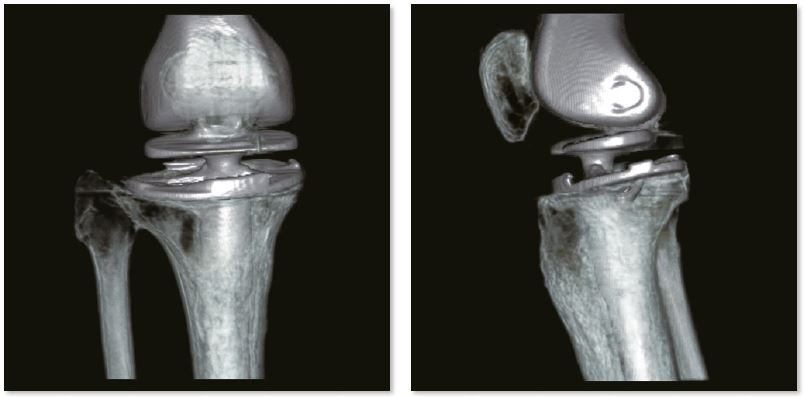

Заміна колінного суглоба

3D зображення коліна

Звичайне зображення

Зображення з SEMAR